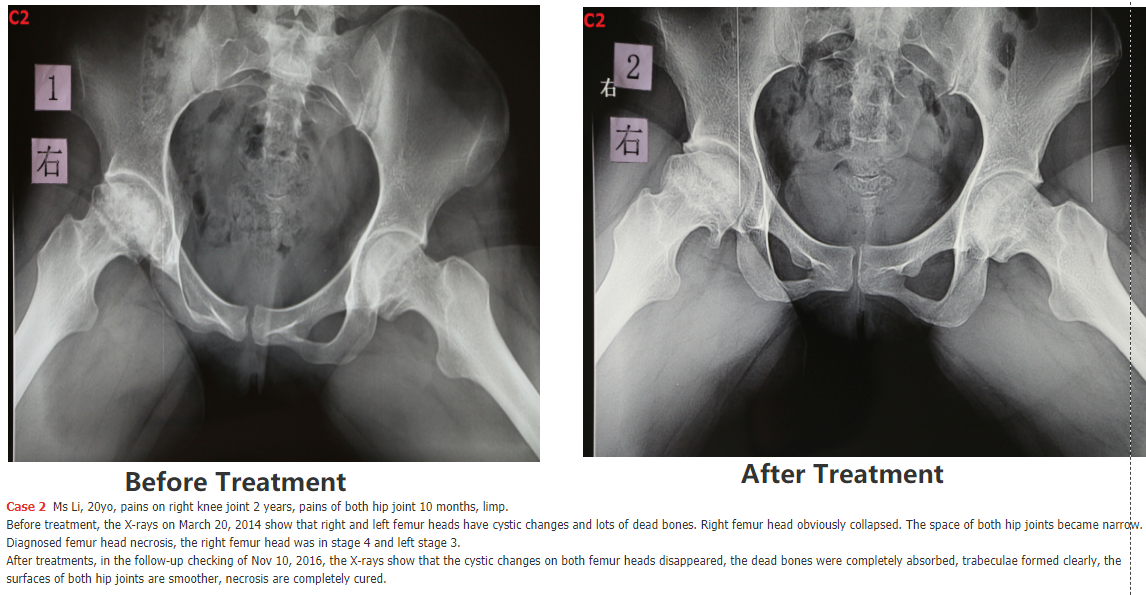

5. following are SOME Chinese patients we have cured - we will add the cases 5, 6, 7, 8, 9, 10, 11, 12.... SOON